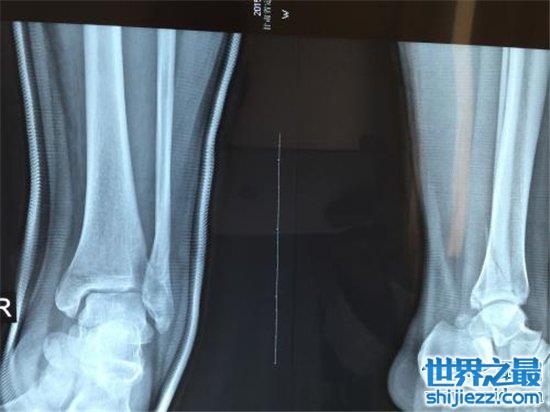

2、踝关节骨折

踝关节就是我们通常说的“脚踝”,是人体骨骼中相当脆弱的一节,也是人体活动必不可少甚至可以说是至关重要的一环。且踝关节属于比较容易受伤的一个部位,一旦踝关节骨折,我们就几乎会陷入无法正常行走乃至不良于行的困难境地。